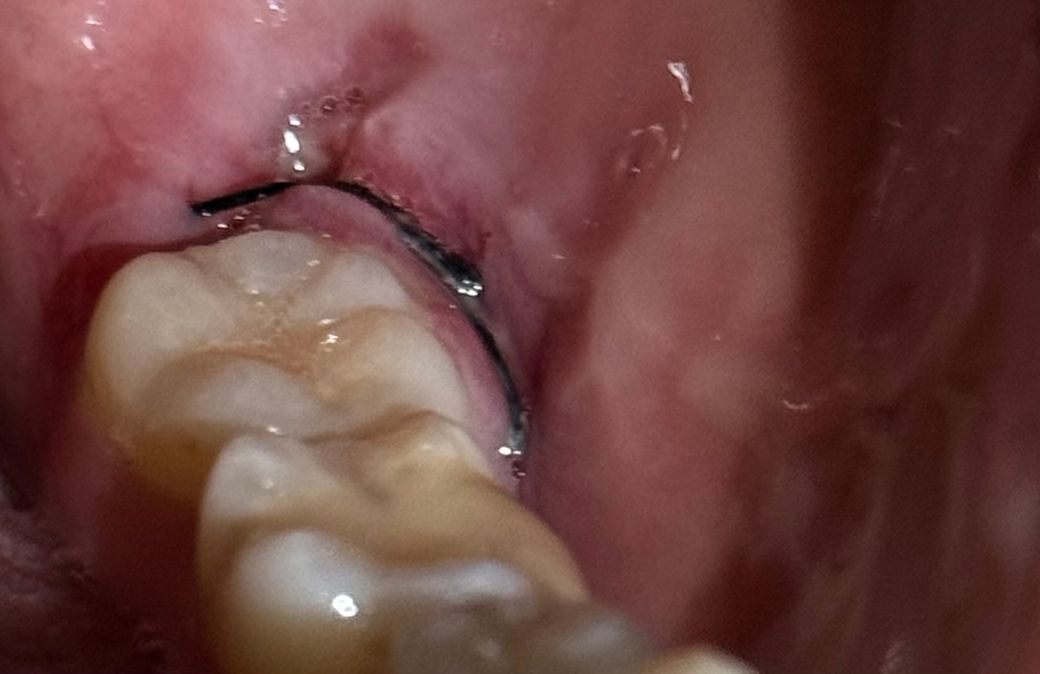

• 1번 째 사진

입 안 보면 잇몸 벽? 쪽에 하얀게 쭉 생겼는데 염증 그런군 아니겠죠......

발치와 관련된 흔적은 아니고 씹어서 생긴 교흔같습니다